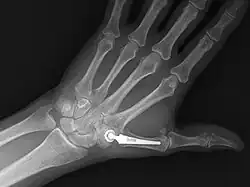

Am bekanntesten sind wohl die künstlichen Hüftgelenke. Heute stehen auch Endoprothesen für weitere Gelenke zur Verfügung (Kniegelenk, Schultergelenk, Sprunggelenk-Endoprothese sowie Ellbogengelenks- und Fingergelenksprothesen), wobei arthrotische Gelenkveränderungen eine häufige Indikation darstellen. Als Gelenkersatz ist auch die Bandscheibenprothese anzusehen. Auch in der Veterinärmedizin (Hunde/Katzen) hat das künstliche Hüftgelenk Einzug gehalten.